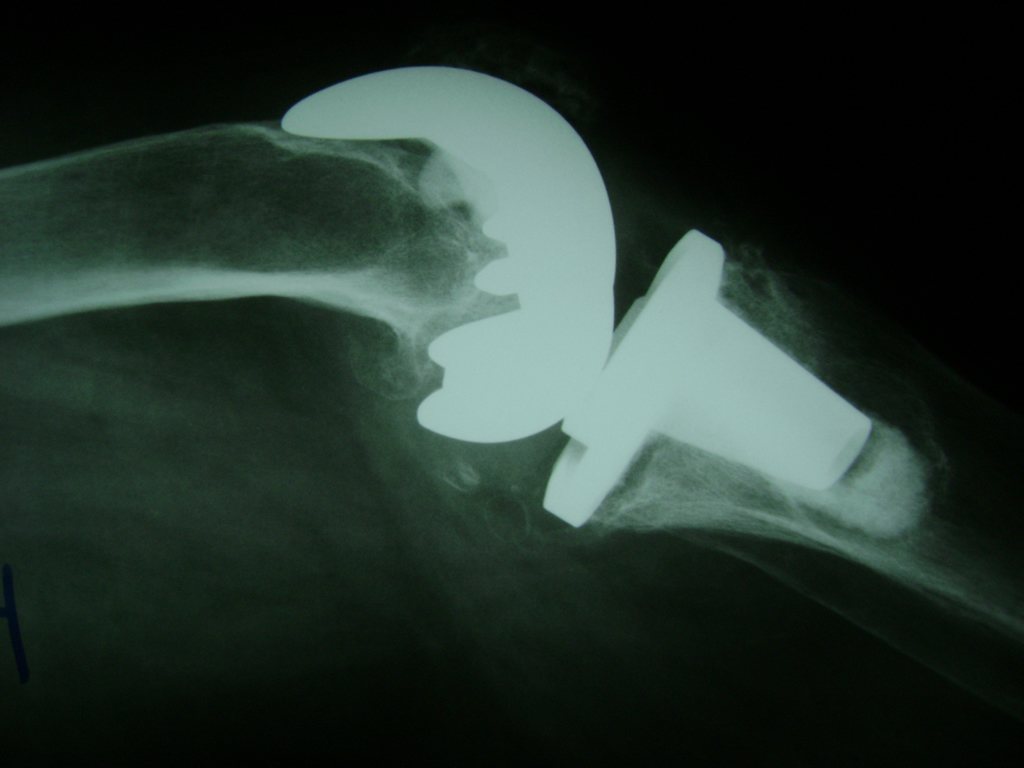

Cirugías de Hombros - Rodilla

La artroscopia de rodilla es un cirugía en el cual la estructura interna de la articulación es examinada ya sea para realizar un diagnostico o para realizar un tratamiento, este procedimiento se realiza utilizando un instrumento parecido a un pequeño tubo llamado artroscopio.